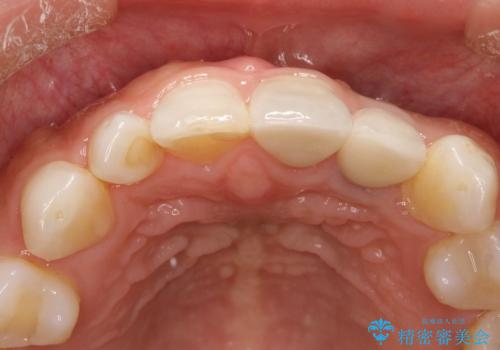

- 左上の前歯が外れそうとのことで来院されました。

レントゲンを撮影すると、不適合のかぶせ物が装着されており、根管治療も不十分でした。

左上の1番目、2番目の歯を根管治療からの再治療を行う計画としました。

レントゲン上でも適合の良いかぶせ物が装着できています。